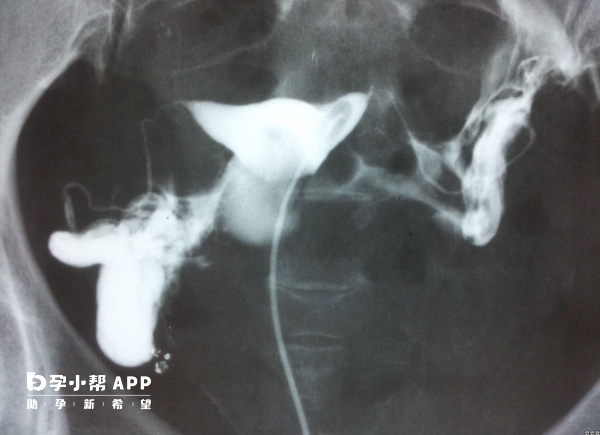

有没有男性精索静脉曲张的图片?不同程度有什么区别?

在临床上把精索静脉曲张分为三个程度,轻度精索静脉曲张,在超声测得精索静脉的直径在2.2-2.7mm之间,中度精索静脉曲张,在超声下测得的精索静脉直径达到了2.8-3.1mm之间,重度精索静脉曲张,在超声下测得的精索静脉直径达到了3.1mm以上。一般轻度的精索静脉曲张是没有什么特别的症状的,也是不需要进行特别的治疗的,但是中度和重度的精索静脉曲张就需要引起重视了,可能会导致睾丸萎缩,造成少精、弱精、...